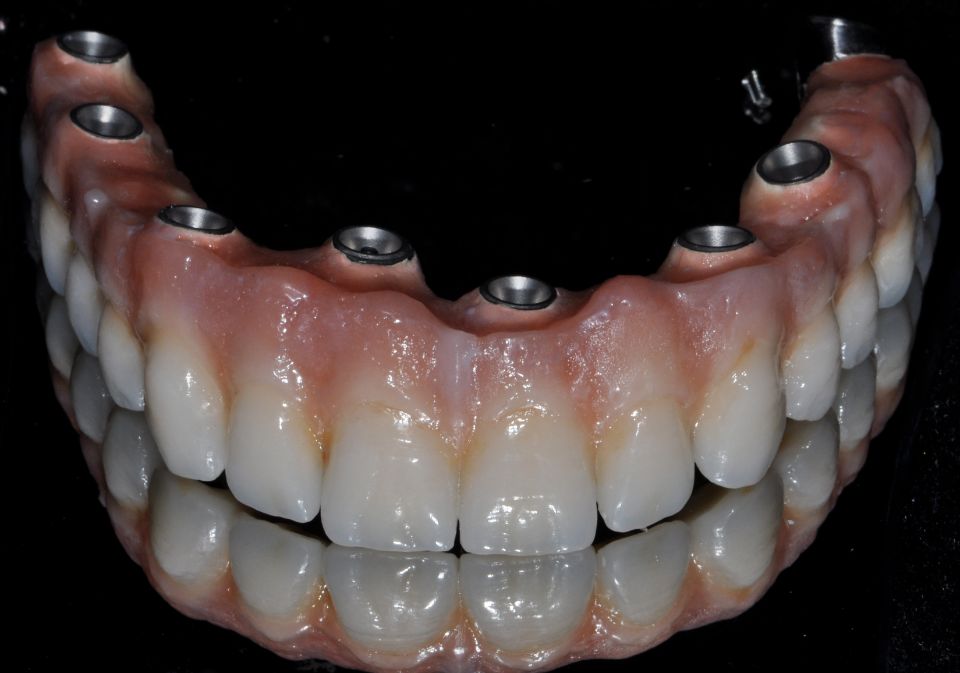

La implantología es la especialidad odontológica que se ocupa de la sustitución de la raíz del diente perdido.

La sustitución se hace mediante una pequeña intervención quirúrgica para colocar una pieza de titanio dentro del hueso maxilar.

El implante tiene una rosca en su interior donde posteriormente se enroscará el pilar que soportará la corona protética.

Después de la valoración del implantólogo y un diagnóstico muy esmerado por parte del equipo profesional se plantean diferentes soluciones. Dependiendo del problema planteado que puede ser: pérdida unitaria, pérdida múltiple o desdentado completo...se realizará la técnica precisa con el fin de mejorar la calidad de vida del paciente.

La implantología es una de las áreas médicas que más ha evolucionado en los últimos años. Eso hace que la fiabilidad y la comodidad del paciente aumente.